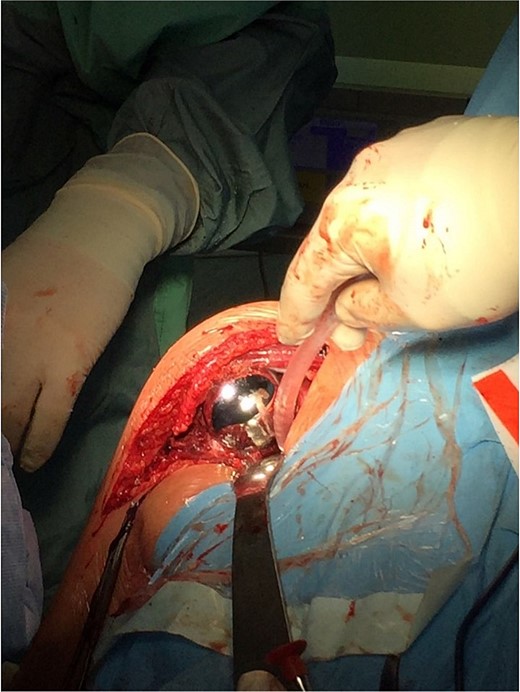

On 17 December 2020, an arthrosurface procedure on the humeral head was performed (i.e. replacement of the damaged articular surface with an implant that recreates its desired shape) using the OVO Motion Shoulder Arthroplasty System Med & Care. The surgery was performed under general endotracheal anesthesia. During the surgery, the beach chair position of the patient with delto-pectoral approach was performed. The arthrotomy was performed by temporarily dissecting the tendon of the subscapular muscle. Additionally, an intraoperative SLAP lesion was found, and the tenodesis of the long head of the biceps muscle was performed. The operation was performed according to the standard surgical procedures during which an endoprosthesis of the humerus head articular surface (OVO) (diameter 48 × 52 mm) was implanted and cemented.

The operation procedure took ~1 hr. Below are intraoperative photos after the endoprosthesis has been placed (Figs 6–8).